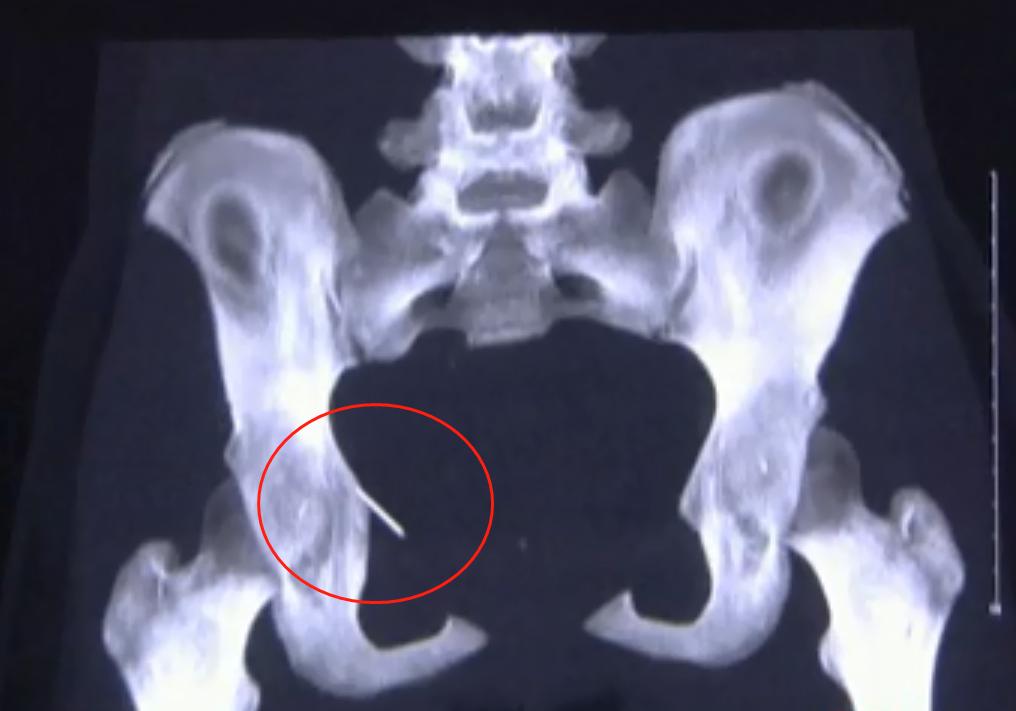

医生为小丽安排了细致的检查,但拿到CT的第一秒,所有人都震惊了!

“骨盆这里明显有一个亮点,应该是一个金属异物。”

仔细研讨后,医生分析,这是一颗长约两三厘米的尖锐断针,并且藏在骨盆内好几年了。

最重要的是,根据其所在位置,还能分析出断针一直跟着肌纤维的运动在游走。

结果看到螺纹CT后,医生全都倒吸了一口凉气,因为断针刚好就在直肠阴道和盆壁之间。

这是一个非常致命的位置,一旦断针划破直肠,或者刺穿子宫,都会引起大出血,影响今后的生育。

甚至严重的还可能导致不孕,威胁到生命安全。